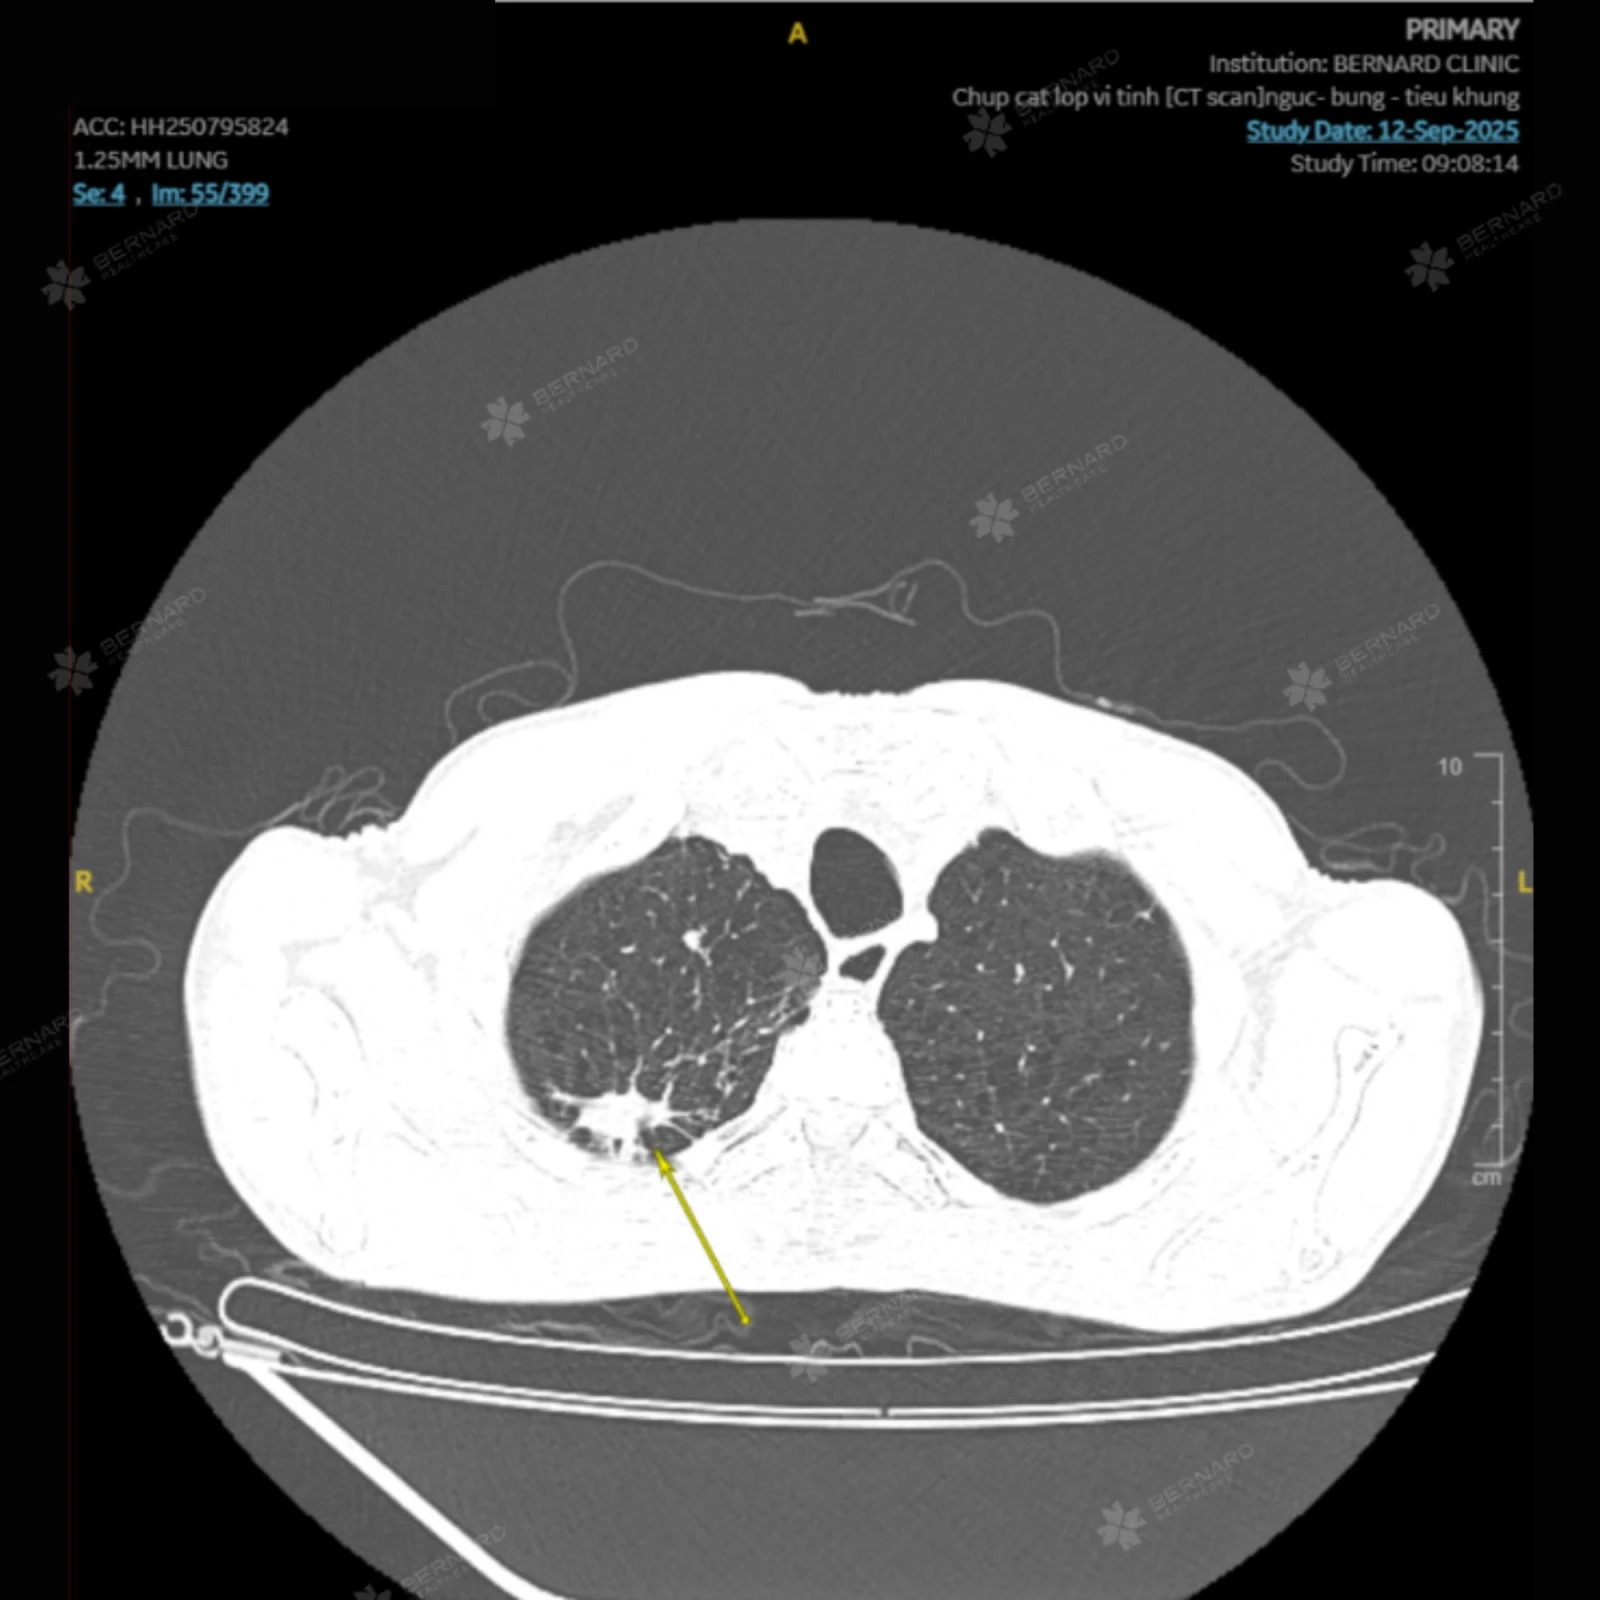

Trước những biểu hiện kéo dài và yếu tố nguy cơ hiện hữu, bác sĩ Bernard đã chỉ định ông M. thực hiện các khảo sát chuyên sâu để đánh giá toàn diện tình trạng phổi. Kết quả chụp cắt lúc vi tính (CT) ngực có tiêm thuốc cản quang ghi nhận:

- Khí phế thủng lan tỏa hai phổi

- Các vùng xơ - xẹp và giãn phế quản phân thùy S1-2 phổi phải

- Những mảng xơ - xẹp rải rác tại S1-2 phổi phải và thùy dưới phổi trái

- Hình ảnh mô kẽ dạng nốt và dạng lưới, kèm dày vách liên tiểu thùy

Mặc dù các tổn thương bắt thuốc sau tiêm nhưng mức độ không đồng nhất, khiến bác sĩ Bernard phải cân nhắc tổn thương với nhiều khả năng khác nhau như viêm mạn tính, tổn thương phổi phức tạp cho đến các bệnh lý ác tính (tổn thương di căn).